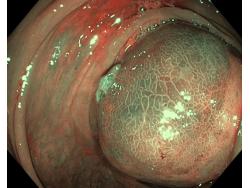

Obrazy endoskopowe

Polipy

Nowotwory przewodu pokarmowego